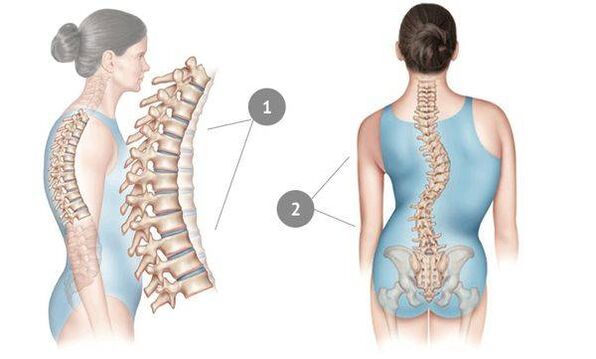

Osteochondrose kaldes normalt dystrofiske forandringer i rygsøjlens knogle og bindevæv. Rygsøjlen viser sig at være ude af stand til at klare normale belastninger – og det kommer primært til udtryk i udseendet af smerte, som først kommer vagt til udtryk, men med tiden bliver mere og mere intens.

I denne sygdom bliver kernen af rygmarvsskiven tyndere og tørrer ud, det fibrøse væv omkring det begynder at forringes, og bruskvævet undergår negative ændringer. Rygsøjlen viser sig at være ude af stand til at klare normale belastninger – og det kommer primært til udtryk i udseendet af smerte, som først kommer vagt til udtryk, men med tiden bliver mere og mere intens. Men med betydelig stress - en stillesiddende livsstil, stillesiddende arbejde, konstant stress, dårlig kropsholdning og rygskader - påvirker osteochondrose før eller siden thoraxregionen. Sygdommen anses for meget almindelig - hver tredje voksen lider af den.

Avanceret osteochondrose af rygsøjlen udtrykkes i skoliose; nogle gange spreder sygdommen sig til halshvirvlerne og forårsager stemmetab.